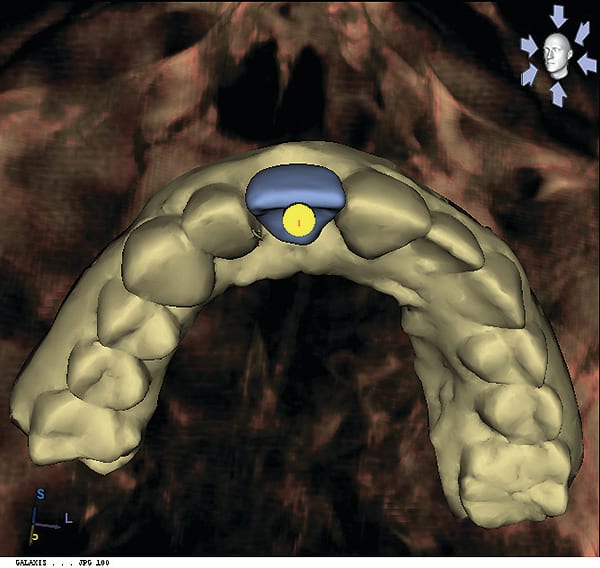

Figure 12

Figure 12 Incorporation of an ideal fixed temporary provisional into a digital implant proposal (reverse engineering concept via CEREC, Sirona Dental, Inc.).

Figure 13

Figure 13 Incorporation of an ideal fixed temporary provisional into a digital implant proposal (reverse engineering concept via CEREC, Sirona Dental, Inc.).